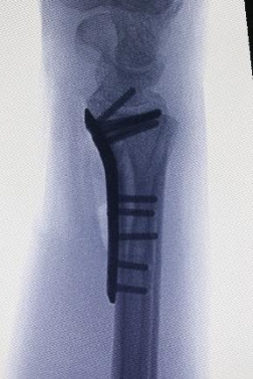

Konservatif tedavinin uygun olmadığı durumlarda cerrahi tespit önerilebilir. Distal radiusun sabitlenmesinde artık en yaygın yaklaşım, bileğin volar yönündendir. Bu, anatomik volar kilitleme plakasının kullanılmasını gerektirir. Birçok avantajı arasında daha az fark edilen bir cerrahi yara izi yer alır; kilitleme vidalı titanyum plaka daha iyi stabilite sağlar ve özellikle osteoporotik kemikleri olan hastalar için endikedir. Ulnar stiloid tabanda kırılmışsa kırığın onarılması tavsiye edilir.

Cerrahlar, kemik iyileşirken kırık kemiği doğru pozisyonda tutmak için birkaç alternatife sahiptir :